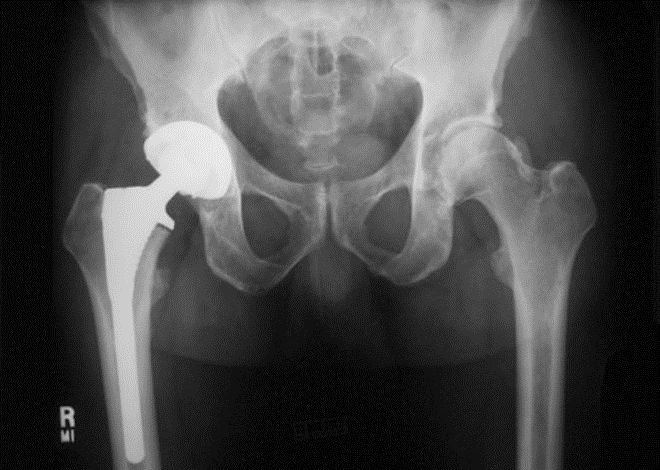

术后5天,脱位

术后4月,再一次脱位

全髋置换术后早期(5年内)失败占所有髋关节置换术后翻修病例的39%

早期失败的原因:-不稳定-脱位 (33%)-无菌性松动 (30%)-感染 (14%)-骨溶解 (5%) -半髋置换术后髋臼侧磨损(15%) -假体周围骨折(3%)

单看股骨侧,大转子顶点和股骨头旋转中心的关系恢复了

但髋臼旋转中心点上移了造成了患肢术后肢体短缩因此如果术中发现髋臼旋转中心点有上移或下移,股骨假体也应相应的吊高或下沉以获得双下肢等长

术后股骨头旋转中心点增高,导致患肢延长